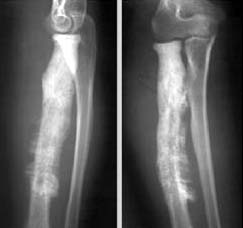

影像学表现:(1)X线平片:早期(3-5天)皮下软组织肿胀,肌间隙模糊;两周后(10-14天始)骨质破坏、骨膜增生(层状),骨膜新生骨包壳形成;部分形成死骨(抗生素广泛应用致少见)。

2周以后:1、骨质疏松:局限;2、骨质破坏为主→骨干;3、骨膜增生:骨包壳;4、骨质坏死:死骨 ;5、轻度骨质增生

(2)CT:能发现细小的破坏区和细小的死骨;(3)MRI:在显示髓腔及软组织受累范围优于平片和CT。充血、水肿、渗出和脓肿在T1WI为低信号, T2WI为高信号,脓腔壁可明显强化。

2、慢性化脓性骨髓炎(慢性骨脓肿(Brodie脓肿):由低毒性 葡萄球菌引起,症状轻。干骺端类圆形 破坏区,有硬化边,偶见小死骨,无骨膜增生,硬化性骨髓炎):增生硬化为主、死骨、瘘管

X线平片与CT:1)病变时愈时发,软组织瘘管形成;(2)骨质破坏的同时,以增生硬化为主;骨干增粗,髓腔闭塞,骨膜增生(形成骨壳),死骨仍存(3)愈合:a、破坏区与死骨消失;b、增生硬化吸收,髓腔沟通。

X线表现:1、骨质增生硬化为主。2、骨质破坏轻。3、有脓腔和死骨。4、骨干增粗、变形。5、髓腔变窄甚至闭塞。

慢性硬化性骨髓炎

X线表现

1、骨质增生硬化

2、骨膜增生,髓腔变窄

3、骨干增粗